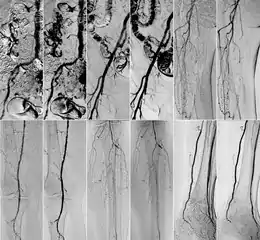

In 2018 Gyánó M. et al. compared the quality of DVA and DSA (digital subtraction angiography) images in a prospective observational crossover study, which involved the analysis of 232 image pairs of 42 patients undergoing lower limb x-ray angiography (performed by using iodinated contrast agent) between February and June 2017. Methods included the measurement of SNR (signal-to-noise ratio) and visual quality comparison.[1]

Although other factors like spatial resolution, sharpness, and object size may contribute to image quality and object perceptibility, noise places a fundamental limitation on the ability to recognize structures on low-contrast images and that was the main reason why the SNR measurement method was chosen. The results showed 2-3 times higher SNR values in the case of DVA images compared to traditionally used DSA images, which has indicated that DVA has the potential to improve the ability to view blood vessels, since a higher SNR value indicates lower noise levels.

Qualitative comparison has been performed by three vascular surgeons and three interventional radiologists, with about 17 years of experience on the average. In an online visual questionnaire, which showed DVA and DSA image pairs of the same anatomical regions, raters were asked to choose the image which they found to be more useful for making the diagnosis. Overall, the raters judged the kinetic images better in 69% of all images. Regarding different anatomical regions, the raters agreed that the DVA was significantly better for talocrural and popliteal regions.